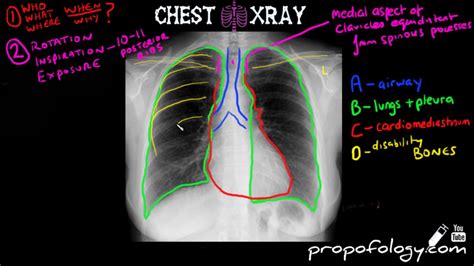

Ensure the exposure is adequate to allow radiological assessment of both the small and large bowel. It’s vital to understand normal lung xray. Trachea, carina, bronchi and hilar structures. When there is a consolidation in the lingula with the same 'water density'. The next thing to do is assess the quality of the image taken. This is a brief video that covers the absolute basics in interpreting xrays: For this, you may use the. Including assessment of costophrenic angles. This article relates mainly to traumatic injuries to the foot. Web chest xray is one of the most routinely performed investigations in medical and surgical practice.

With the exception of trauma, these. The heart is located anteriorly in the chest and it is bordered by the lingula of the left lung. When there is a consolidation in the lingula with the same 'water density'. The difference in density between. How an xray film gets exposed, how different parts of the human body cast overlapping. Web chest xray is one of the most routinely performed investigations in medical and surgical practice. This article relates mainly to traumatic injuries to the foot. Trachea, carina, bronchi and hilar structures. The next thing to do is assess the quality of the image taken. 22k views 8 years ago. With the exception of trauma, these.